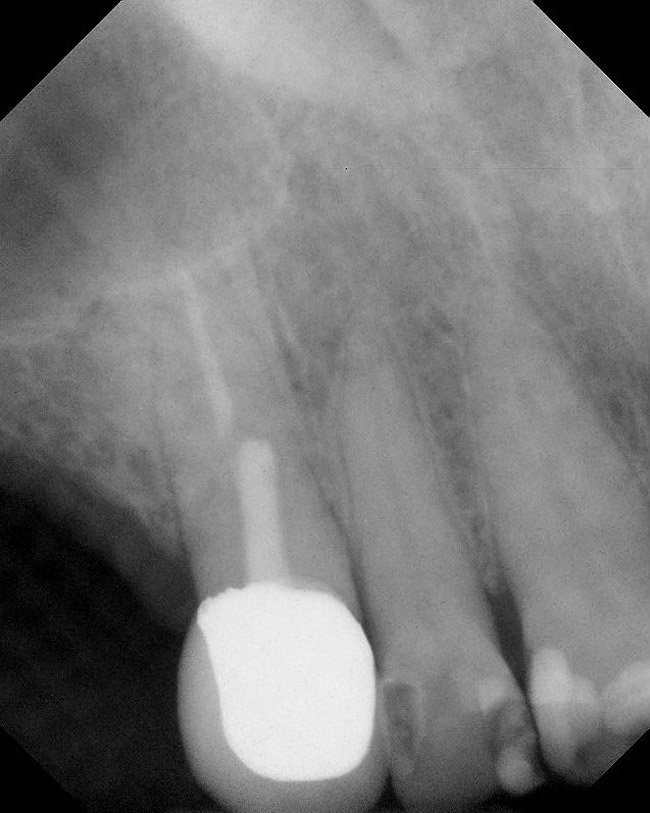

Figure 1  Buccal and radiographic views of posterior edentulism with significant sinus pneumatization in the molar region.

Figure 1

Figure 2  Buccal and radiographic views of posterior edentulism with significant sinus pneumatization in the molar region.

Figure 2